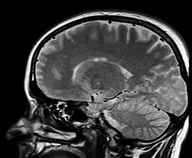

Clare Walton at the Alzheimer’s Society said: ‘This research has identified an age-related protein in mice that damages an area of the brain that is important for memory. This interesting study highlights the importance of basic research in helping to find new targets for drugs to help stop cognitive decline.